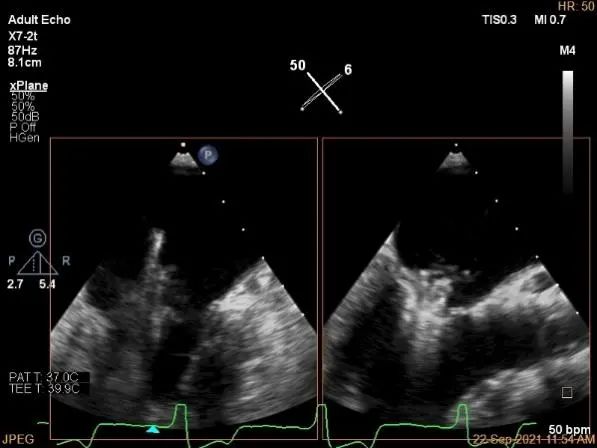

术中超声

3D:P1区脱垂并腱索断裂,Width:11.4mm

3D-color:重度MR,4级

麻醉状态下肺静脉血流频谱

MVA:7.8cm²,平均跨瓣压差:1mmHg

房间隔穿刺点选择

穿刺高度:4.08cm